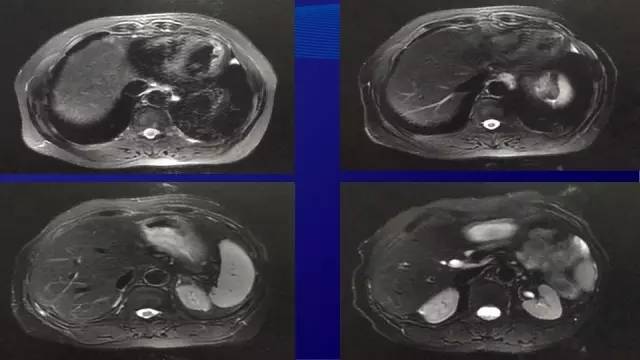

● 2014-11复查肝脏MRI,肝内转移灶增多,增大

● 2014.11 患者自行就诊于介入科,要求行肝脏肿瘤消融术,将肝左外叶(2枚)与右肝(1枚)转移灶进行微波消融,其余病灶(新发两枚)未处理

● 2015.07行肝转移灶切除术

● 术中见肝II, III段7*6*4厘米质硬灰白色结节,VI段6*5*7厘米质硬灰白色结节,切除肝II,III(2枚)和VI段的肿物(2枚)

● 术后病理:(肝)中分化腺癌,免疫组化符合肠癌肝转移。其中2枚消融病灶坏死成分约80-90%;另两枚病灶坏死成分约30-40%,纤维化约20%。